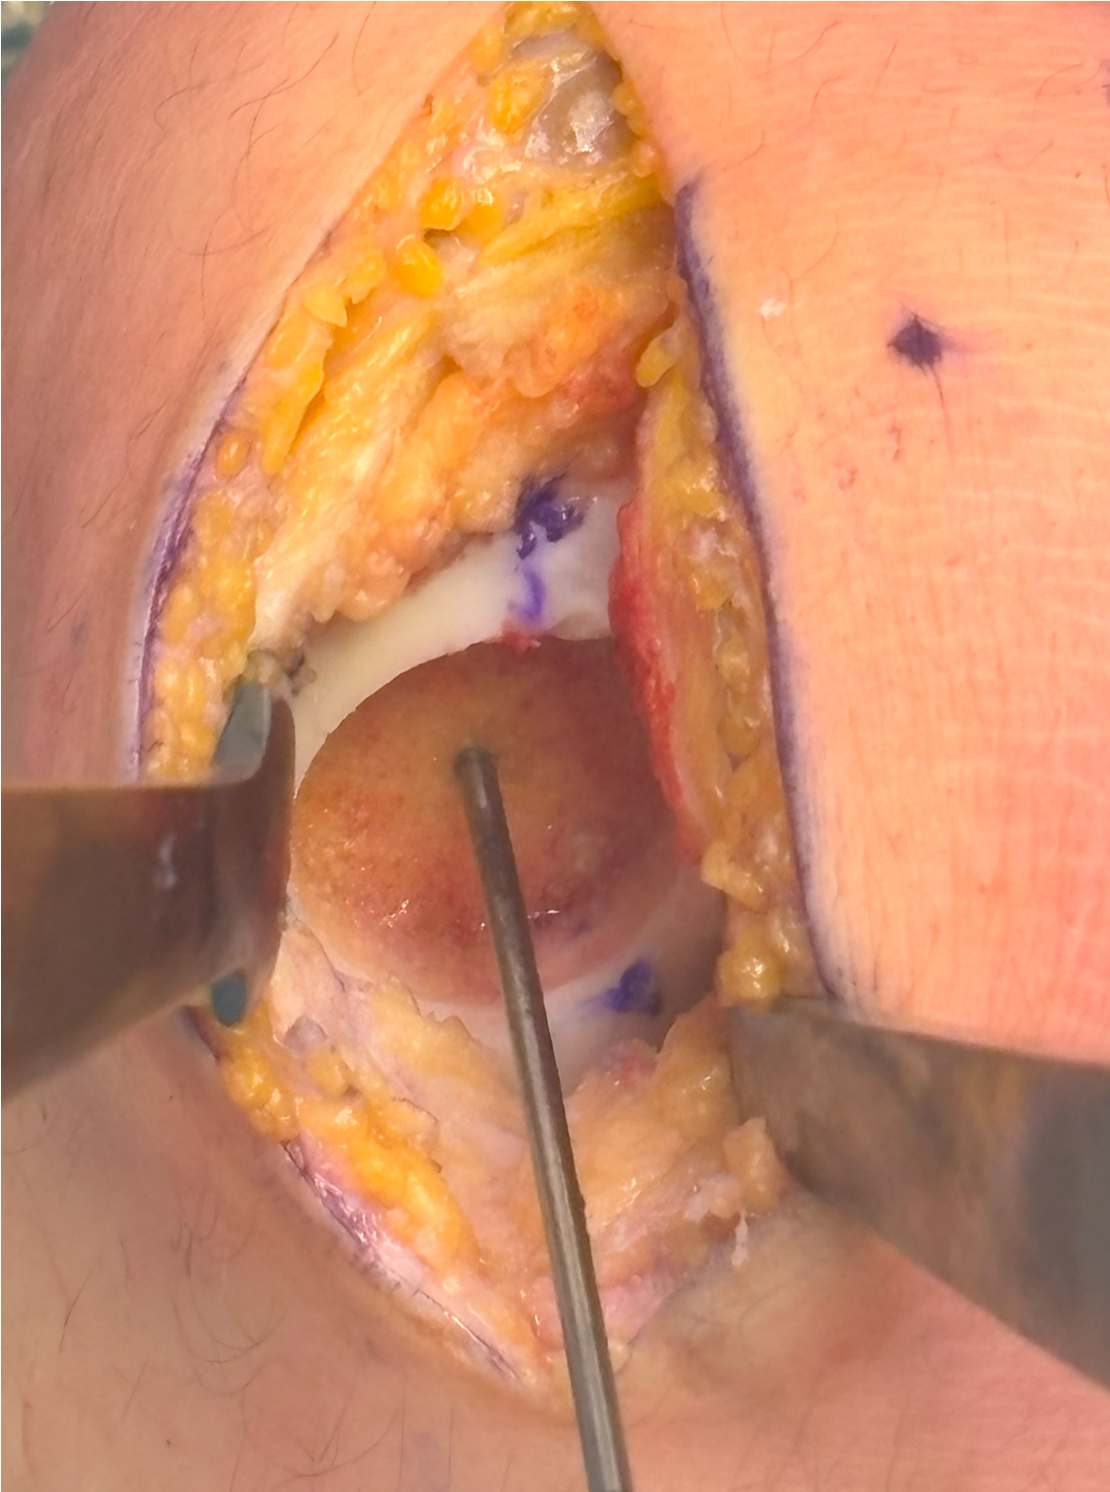

Implantation

- medial or lateral parapatellar approach

- create sharp stable margins

- curette base

- control bleeding with adrenalin soaked gauze to avoid graft displacement

- size defect with foil - graft cannot be prominent or will displace with ROM

- secure with fibrin glue / Tisseal

- ensure graft stability with knee range of motion